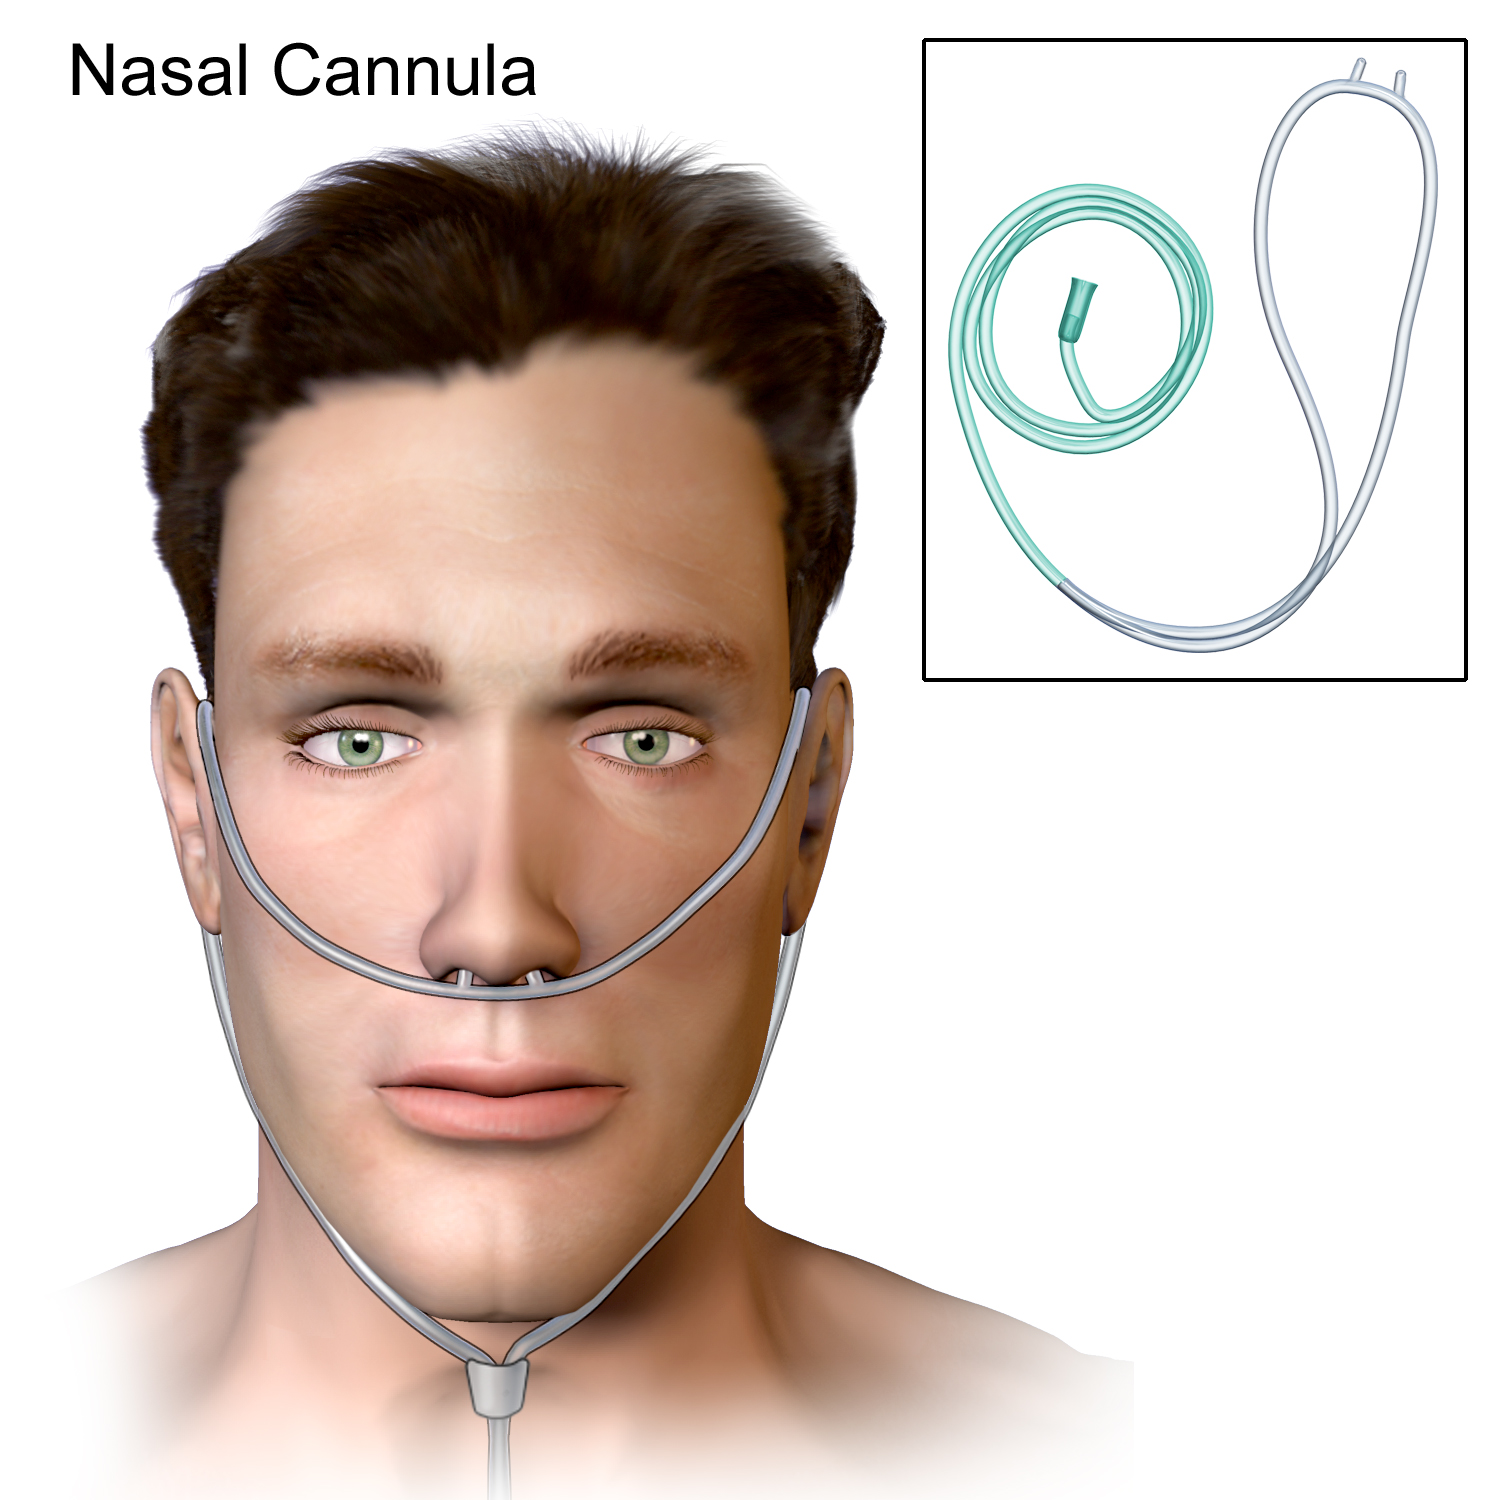

- Supplemental Oxygen – usually indicated for majority of the patients, can be delivered using devices such as nasal cannulae or Venturi masks.

- High flow nasal cannulae – consists of wider – bore prongs and offers humidification and titration of oxygen concentrations to be delivered.